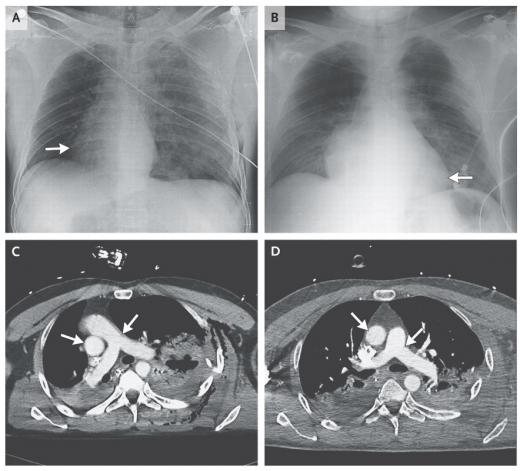

의료진은 남성의 가슴부위를 엑스레이와 컴퓨터 단층 촬영장비로 찍어 내부를 살폈고 놀라운 광경을 목격했다. 이 남성의 심장이 가슴 중앙 왼편에서 정확히 90도 꺾어져 오른편으로 이동해있던 것이다.

처음에 의료진인 오토바이 사고로 몸이 격렬하게 뒤틀리며 심장위치가 이동한 것이 아닐까 추측했다. 하지만 세부 조사가 진행되면서 환자의 폐에 새로운 상처가 발견됐고 여기서 공기가 새어나오고 있었다. 의료진은 보고서에 기록하길, 폐에서 뿜어져 나오는 공기의 증강이 심장 위치를 바꾼 주요 원인으로 지목했는데 이후 남성 환자 가슴내부에 꽉 들어찬 공기가 배출된 후 24시간이 지났을 때, 심장위치는 정상적으로 돌아왔다.